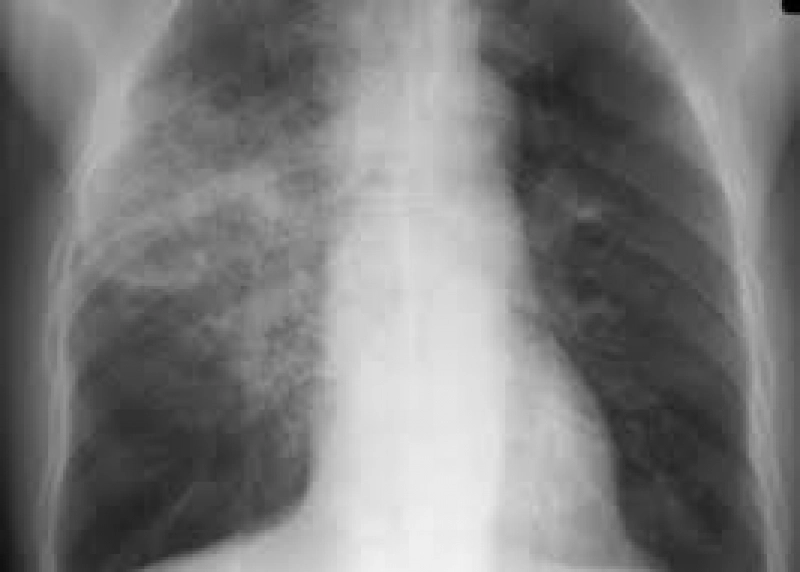

În primele zile ale lunii, peste 300 de persoane din Vâlcea au fost afectate de viroze respiratorii și pneumonii. Din acestea, 34 de pacienți au necesitat spitalizare din cauza complicațiilor, conform informațiilor oferite de Direcția de Sănătate Publică (DSP) Vâlcea, citate de Agerpres.

Reprezentanții DSP au detaliat, pentru Agerpres, că în perioada 29 septembrie – 5 octombrie, medicii de familie au raportat 248 de cazuri de infecții acute ale căilor respiratorii superioare (IACRS), dintre care 122 au fost în rândul copiilor. De asemenea, au fost diagnosticate 76 de persoane cu pneumonii, dintre care 35 erau copii.

În aceeași săptămână, 16 copii și 14 adulți cu pneumonie au necesitat internarea în spitale. Totodată, 3 copii și un adult au fost spitalizați din cauza virozelor, conform datelor furnizate de DSP Vâlcea.